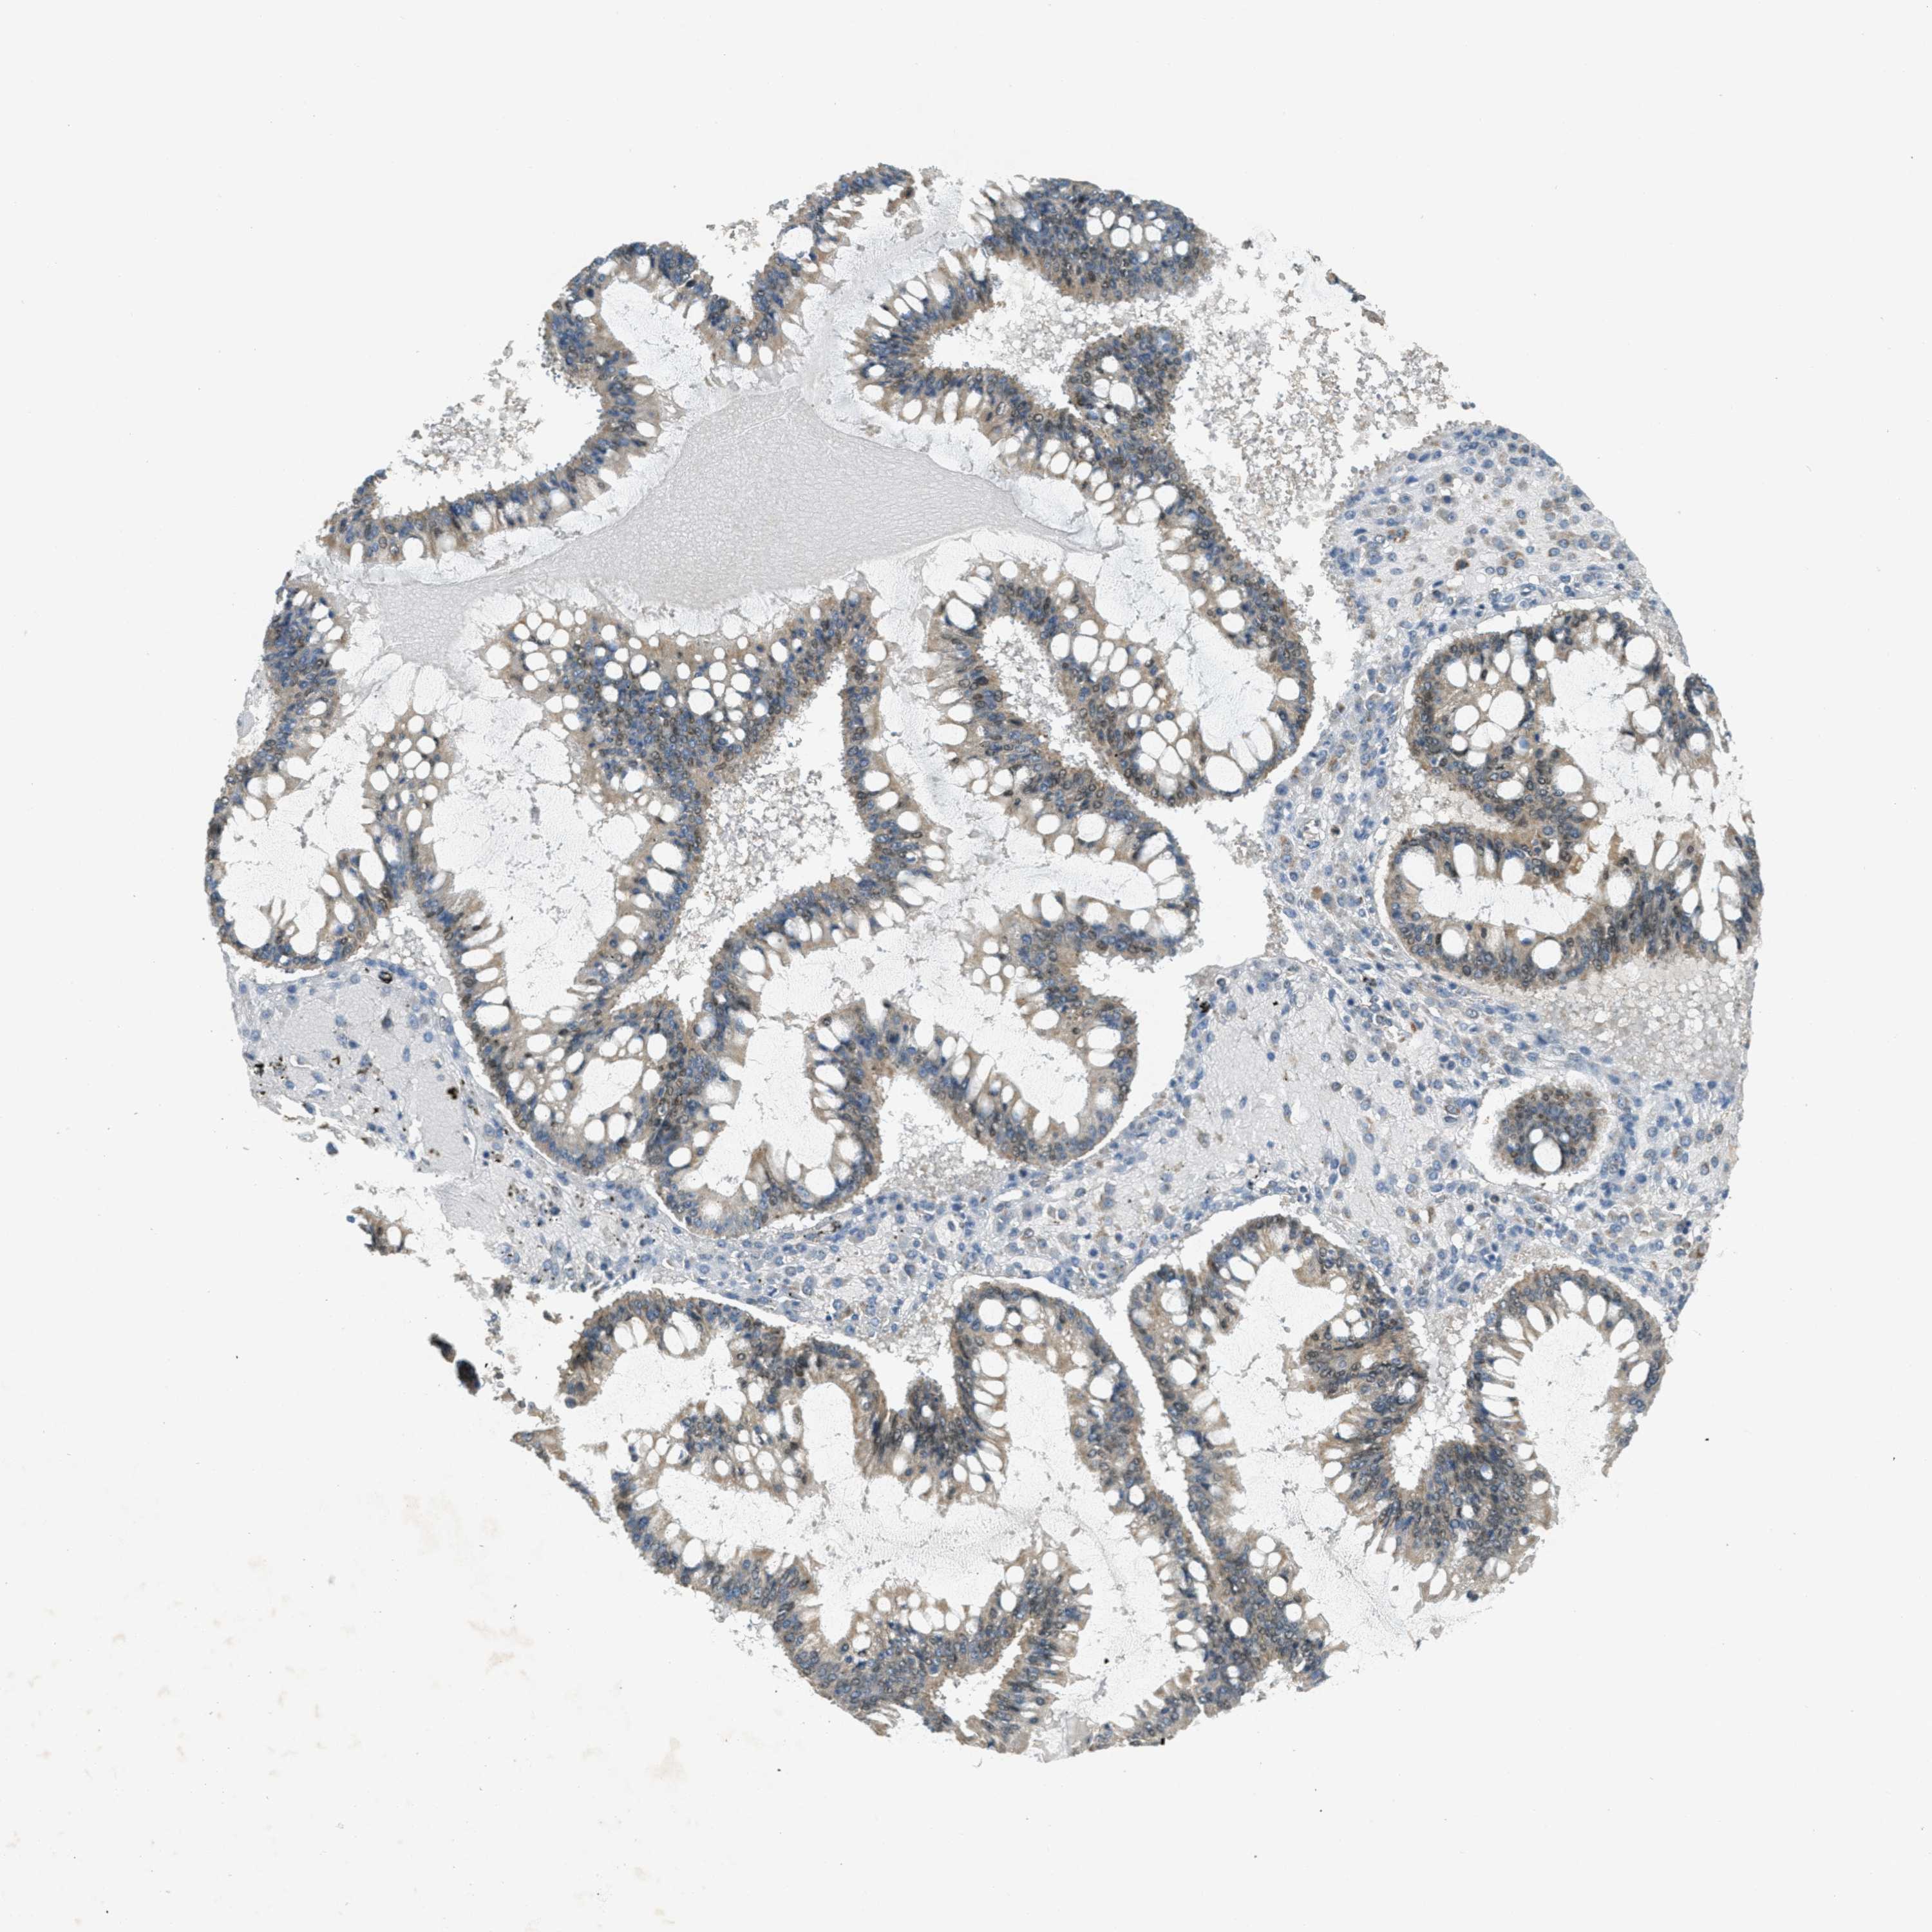

OVARIAN CANCER - Protein expressioni

A mouse-over function shows sample information and annotation data. Click on an image to view it in a full screen mode. Samples can be filtered based on level of antibody staining by selecting one or several of the following categories: high, medium, low and not detected. The assay and annotation is described here.

Note that samples used for immunohistochemistry by the Human Protein Atlas do not correspond to samples in the TCGA dataset.

Antibody stainingi

Antibody staining in the annotated cell types in the current human tissue is reported as not detected, low, medium, or high, based on conventional immunohistochemistry profiling in selected tissues. This score is based on the combination of the staining intensity and fraction of stained cells.

Each image is clickable and will lead to virtual microscopy that enables deeper exploration of all samples and also displays staining intensity scores, fraction scores and subcellular localization as well as patient and tissue information for each sample.

Antibody HPA036786

Antibody CAB017849

Carcinoma, endometroid

Cystadenocarcinoma, mucinous, NOS